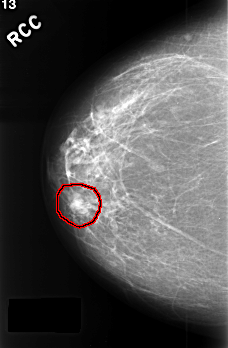

ics_version 1.0 filename C-0390-1 DATE_OF_STUDY 16 5 1996 PATIENT_AGE 66 FILM FILM_TYPE REGULAR DENSITY 2 DATE_DIGITIZED 9 11 1998 DIGITIZER LUMISYS LASER SEQUENCE LEFT_CC LINES 4424 PIXELS_PER_LINE 2928 BITS_PER_PIXEL 12 RESOLUTION 50 OVERLAY LEFT_MLO LINES 4472 PIXELS_PER_LINE 2952 BITS_PER_PIXEL 12 RESOLUTION 50 OVERLAY RIGHT_CC LINES 4520 PIXELS_PER_LINE 2960 BITS_PER_PIXEL 12 RESOLUTION 50 OVERLAY RIGHT_MLO LINES 4560 PIXELS_PER_LINE 2904 BITS_PER_PIXEL 12 RESOLUTION 50 OVERLAY |

FILE: C_0390_1.RIGHT_CC.OVERLAY TOTAL_ABNORMALITIES 1 ABNORMALITY 1 LESION_TYPE MASS SHAPE LOBULATED MARGINS CIRCUMSCRIBED ASSESSMENT 4 SUBTLETY 5 PATHOLOGY BENIGN TOTAL_OUTLINES 1 BOUNDARY |